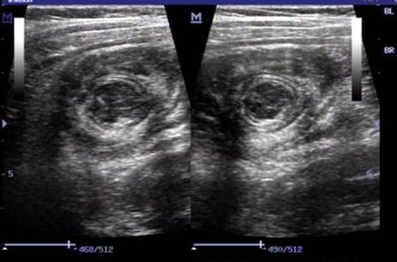

- B超检查:B超是检查肠套叠的最佳办法!相关文献报道,有经验的B超医生对肠套叠的诊断率可以达到100%。